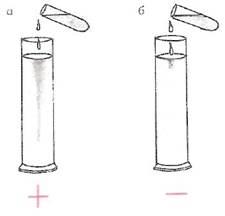

Пробу Ривальта

используют для ориентировочного отличия экссудатов от транссудатов. Она основана на том, что при добавлении капли экссудата с относительно высокой концентрацией белка в раствор уксусной кислоты он мутнеет (рис. 32). В цилиндр емкостью 100 мл наливают дистиллированную воду и подкисляют ее 2-3 каплями ледяной уксусной кислоты. Затем в цилиндр добавляют по каплям исследуемую жидкость. Если при этом появляется своеобразное помутнение раствора в виде белого облачка, опускающегося па дно цилиндра (рис. 32, а), пробу считают положительной,

что характерно для экссудата. Если падающие капли быстро и бесследно растворяются (рис. 32, б), пробу расценивают как отрицательную

(транссудат).

Рис. 32.

Положительная (а) и отрицательная (б) проба Ривальта.